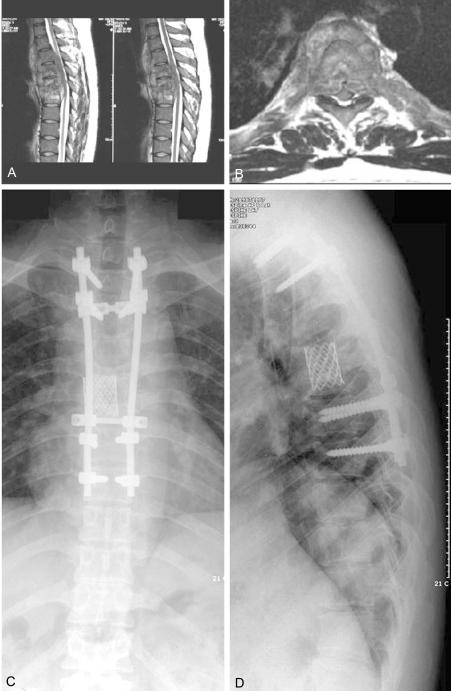

Twenty two patients who had tuberculous spondylitis were treated with anterior radical debridement and their anterior column of spine was supported with a tricortical iliac bone graft (12 patients) or by mesh (10 patients). Supplementary posterior pedicle screw instrumentation was performed in 17 of 22 patients. The combination of surgeries were anterior strut bone grafting and posterior pedicle screws in 12 patients, anterior titanium mesh and posterior pedicle screws in 5 patients and anterior mesh only without pedicle screws in 5 patients. The patients were followed up with assessing the laboratory inflammatory parameters, the serial plain radiographs and the neurological recovery.

RESULTS

The erythrocyte sedimentation rate and C-reactive protein levels were eventually normalized and there was no case of persistent infection or failure to control infection in spite of a mettalic implant in situ. The overall correction of kyphotic deformity was initially 8.9 degrees, and the loss of correction was 6.2 degrees. In spite of some loss of correction, this technique effectively prevented clinically significant kyphotic deformity. The preoperative Frankel grades were B for 1 patient, C for 4, D for 4 and E for 13. At the final follow-up, 7 of 9 patients recovered completely to Frankel grade E and only two patients showed a Frankel grade of D.

CONCLUSIONS

Stabilizing the spine with pedicle screws and/or titanium mesh in patients with tubercuous spondylitis effectively prevents the development of kyphotic deformity and this did not prevent controlling infection when this technique was combined with radical debridement and anti-tuberculous chemotherapy.